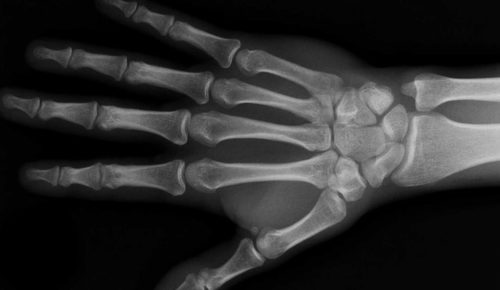

Utilitarianism, the Gospel and the Gift of an Injured Wrist

I have a confession to make, in my heart of hearts, I am a utilitarian. I love useful things and I love things because they are useful. When I chose...